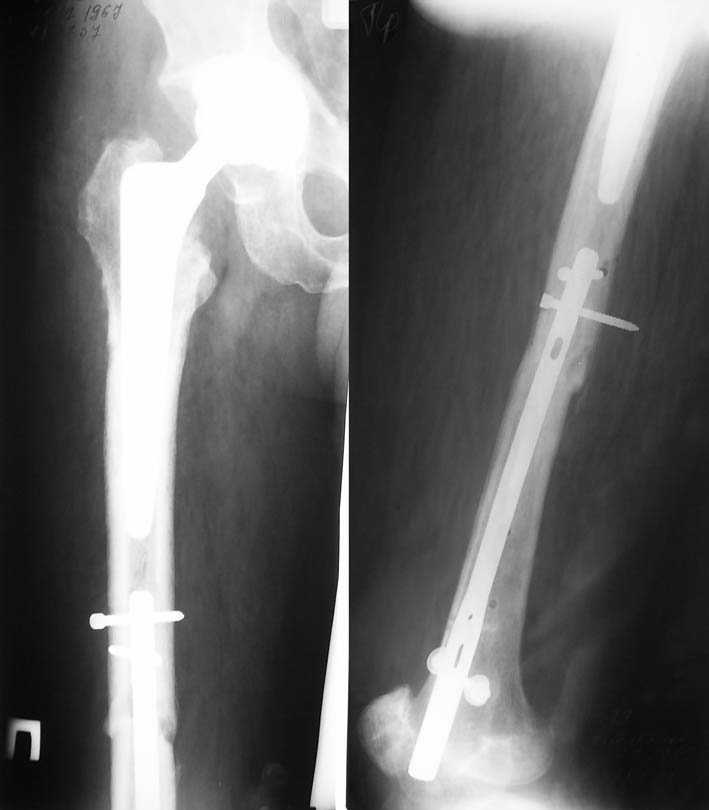

Уважаемые коллеги. Благодарим за дискуссию. Мы решили выполнить комбинированную операцию - эндопротезирование тазобедренного сустава и ретроградный интрамедуллярный остеосинтез (одномоментно)